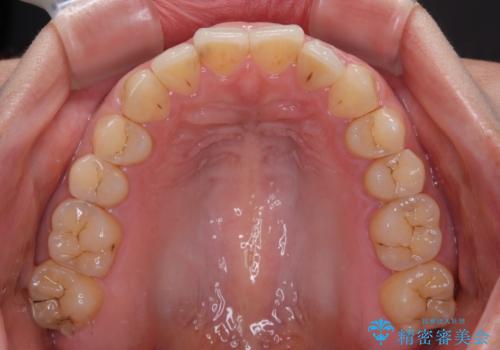

インビザライン矯正で前歯のデコボコを改善

- 前歯のデコボコを気にして来院された患者様です。

目立たないことを最優先にしたいとのことで、デコボコは軽度であったことから、インビザラインにて矯正治療を行うこととしました。

骨格的に下顎骨が左にずれており、上下の正中一致は困難ではありましたが、IPR(歯と歯の間を削る)や後方への移動など組み合わせて、できる限り改善しました。

インビザラインはマウスピースを外している時間が長いと、長期間使用しても前歯のデコボコはあまり改善されません。こちらの患者様は治療期間が長くなり、装着時間が短くなってしまったことで、気になる部分の改善により長期間を要するようになってしまいました。